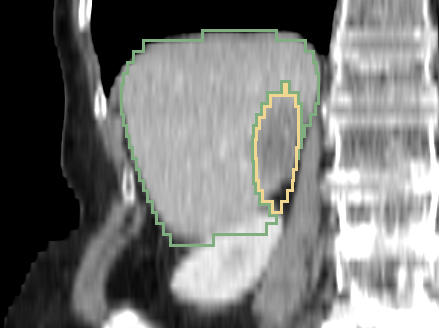

Refer to caption

Figure 23: Example sagittal view slices from the LITS challenge test volumes overlaided with the segmentation boundaries obtained with 3D AH-Net. The livers and the lesions both vary in sizes, morphology and intensities.

Three example volumes are selected from the test image set to demonstrate the effectiveness of our proposed network in Fig. 24, Fig. 25 and Fig. 26. Although we do not have the groundtruth label maps for the testing images, the liver boundaries and the presence of lesions can be visually inspected. The liver lesions normally appear as a dark region within the liver. Without sufficient 3D context, MC-GCN tends to generate false positive regions at the structure boundaries, especially under low image contrast. From the sagittal and coronal views, it is visible that MC-GCN could not generate the correct boundaries close to the top or the bottom of the lesion. By considering the consistency between slices, 3D AH-Net can segment the structures in 3D correctly, although the feature extraction network is transferred from a 2D network. The jagged boundary in the sagittal and coronal view is due to the low resolution in the z direction.